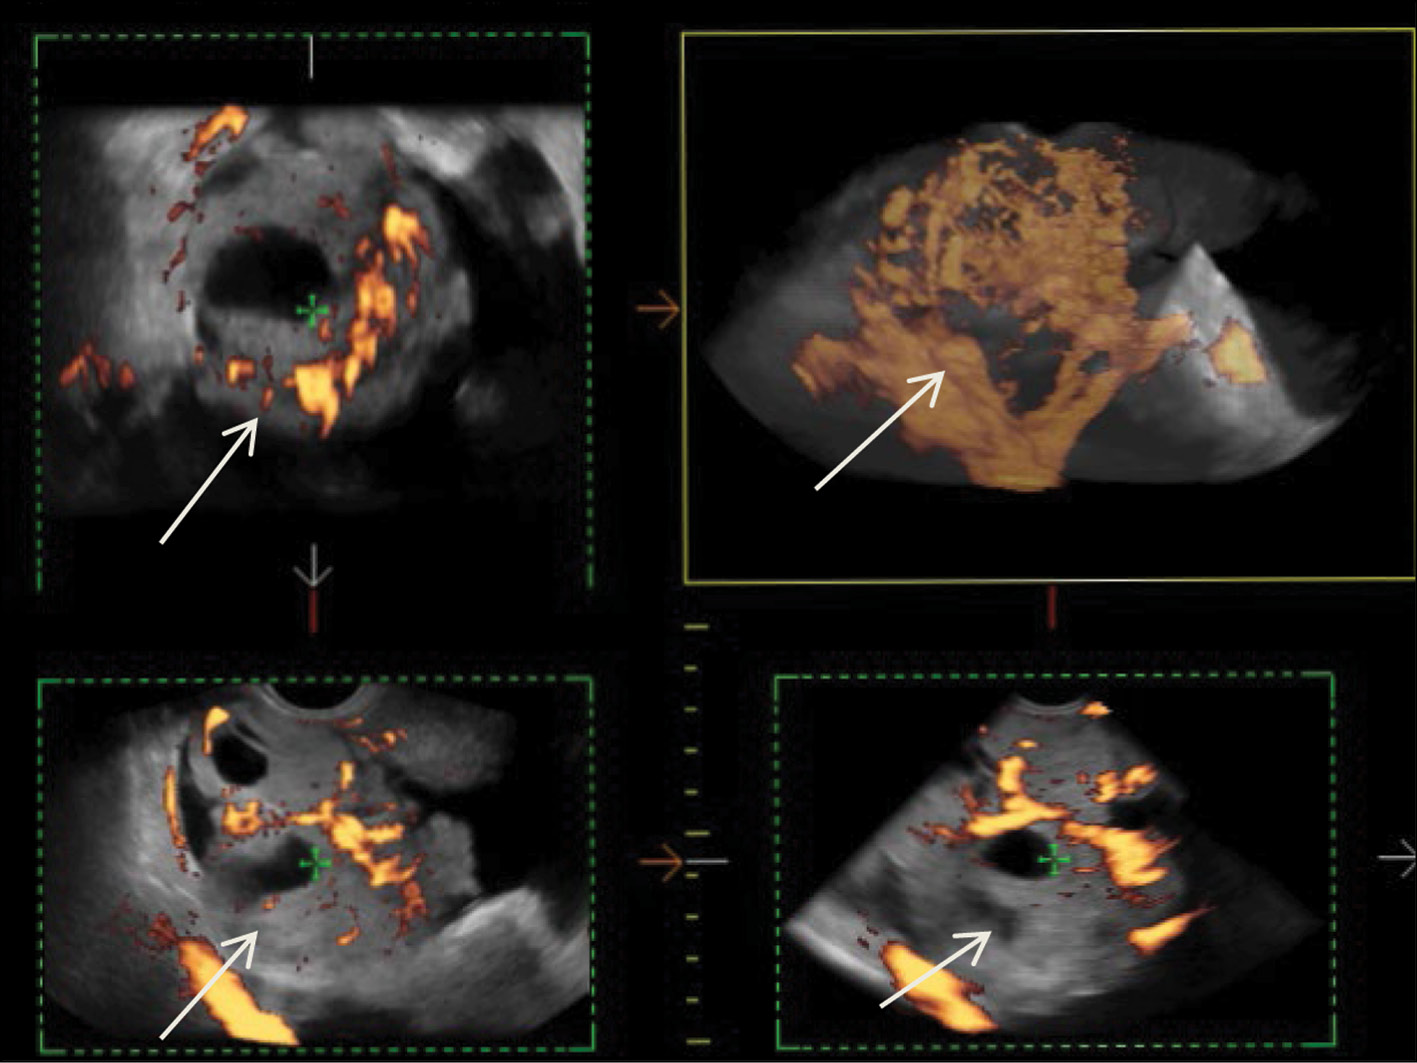

After diagnostic laparoscopy and biopsy of lesions in the pelvic peritoneum performed in another medical institution, complex ultrasonography was performed at the RRCR. An inhomogeneous isohypoechoic mass with areas of an anechoic structure of irregular and rounded shape was found in the projection of the right appendages. Pronounced pathological blood flow in the solid component of the mass, ascites, and carcinomatosis of the peritoneum of the small pelvis were also found. Figure 1 shows a 3D angiogram of the primary malignant struma ovarii on the right ovary.

Fig. 1. 3D angiography of a poorly differentiated malignant struma ovarii on the right (arrows).

eSaote Pro machine US was used; the transvaginal transducer and volume transvaginal transducer were used. Ultrasonography was performed in a standard 2D mode, and high-tech US methods were then used: power Doppler mapping, US computed tomography (CT), and 3D angiography.